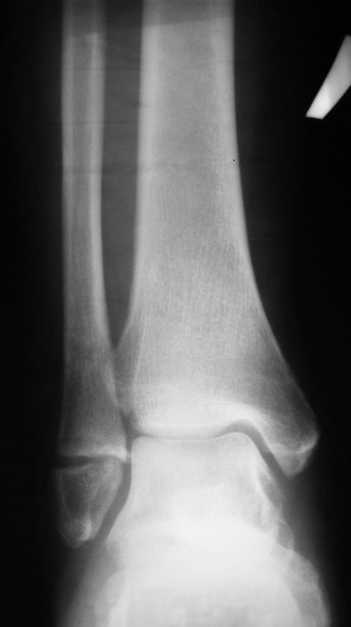

Перелом латеральной лодыжки.

На одном из форумов заспорили о тактике.Женщина 23 года, рост 158, вес 55, профессия: менеджер, хобби: верховая езда, горные лыжи, велосипеды, не курит, сопутствующих заболеваний нет.28 июня упала с лошади.первый рентген:

Иммобилизация гипсовым сапожком до 20 августаНа сегодня- Гипс снаят, со слов больной "Наступать на ногу не больно, но страшно. Сустав и мышцы, конечно, плохо работают."

Вечер добрый! Судя по представленным рентгенограммам (с интервалом почти в два месяца!?) перелом не сросся. Лично я склоняюсь больше в сторону оперативного лечения (с учетом анамнеза пациентки). Но для принятия окончательного решения хотелось бы, для начала, увидеть снимки обоих суставов в сравнении в двух проекциях , а также сравнительные - фас под нагрузкой. При отсутствии жалоб со стороны пациентки на сегодняшний день (при данной рентгенологической картине), они (жалобы) ,скорее всего, появятся позже.

Показано оперативное лечение - металлоостеосинтез латеральной лодыжки маллеолярным винтом. Никаких признаков сращения на сегодняшний день не наблюдается. Непонятно, чем вызвана такая неопределённость врачей. В ортезе нагрузка на сустав на сегодняшний день не просто возможна - необходима.

Ничего удивительного в том, что мнения хирургов разошлись нет, поскольку в целом в мире разные хирурги исповедуют разные тактики лечения переломов наружной лодыжки. Так одни считают, что нужно оперировать даже при смещении в 1 мм, другие допускают 5 мм. В среднем считают «цифрой старта» 2-3 мм. Но все сходятся в том, что нужно ориентироваться на функциональные запросы пациента. Но в вашем случае уже не свежий перелом, а замедленная консолидация со смещением отломков. (Delayed malunion? :-{)

Впрочем и при такой ситуации большинство хирургов придерживается консервативной тактики, поскольку по отдаленным результатам это не приводит к развитию посттравматического артроза и прочим неприятностям. Я в Вашем случае полагаю приемлемым консервативное лечение.

Although fractures of the lateral malleolus without significant medial injury are common, the indications for open reduction of these fractures are still controversial. The maximal acceptable displacement of the fibula reported in the literature has ranged from 0 to 5 mm. In most patients, 2 to 3 mm of displacement is accepted, depending on the functional demands of the patient. Yablon, Heller, and Shouse demonstrated that displacement of the talus accompanies displacement of the lateral malleolus in bimalleolar ankle fractures and emphasized the importance of anatomical reduction of the lateral malleolus in these injuries. Biomechanical studies by Brown et al. and Michelson, Helgemo, and Ahn showed that isolated fractures of the lateral malleolus do not disturb joint kinematics or cause talar displacement with axial loading. Long-term clinical follow-up studies by Bauer, Jonsson, and Nilsson and by Kristensen and Hansen of closed treatment of supination–external rotation stage II fractures reported 94% to 98% good functional results, even with 3 mm of fibular displacement. Yde and Kristensen found the results of operative treatment no better than those of closed treatment in supination–external rotation stage II injuries, even though only 1 of 35 patients (3%) who had closed treatment had anatomical reduction, compared with 28 of 34 (82%) with operative treatment. If the stability of a lateral malleolar fracture is uncertain, stress roentgenograms can be obtained with the ankle in supination and external rotation to detect displacement of the talus indicative of medial injury.

Nonunions of the lateral malleolus rarely require treatment. In reviewing 24 such nonunions an average of 9.6 years after injury, Sneppen found those without displacement to be asymptomatic; some eventually healed spontaneously. He concluded that nonunion of the lateral malleolus in itself does not cause traumatic arthritis or other abnormality and thus does not influence the final result in fractures of the ankle.

Андрей, я всё таки склонен считать, что принципиального разногласия нет. На сегодняшний день рекомендовать оперативное лечение меня заставили следующие факторы:

1. Увеличивающийся диастаз фрагментов,

2. Отсутствие на рентгеновских снимках признаков образования костной мозоли, с одной стороны и

3. Образование кортикальной замыкательной пластинки на проксимальном фрагменте в зоне контакта, с другой,

1- Диастаз увеличивается. За счет чего? Сам дистальный отломок наружной лодыжки как был на месте, так и стоял. Т.е. увеличение диастаза не за счет подвижности и нестабильности, а за счет резорбции.

Данный перелом по классификации Вебера относится к типу А- т.е. дистальнее синдесмоза. В этом месте малоберцовая кость не несёт никакой нагрузки. Прошло только 2 месяца с момента перелома дайте больной что-то типа Air cast на месяц-полтора и полную нагрузку на ногу и сгибательно-разгибательные движения в суставе.